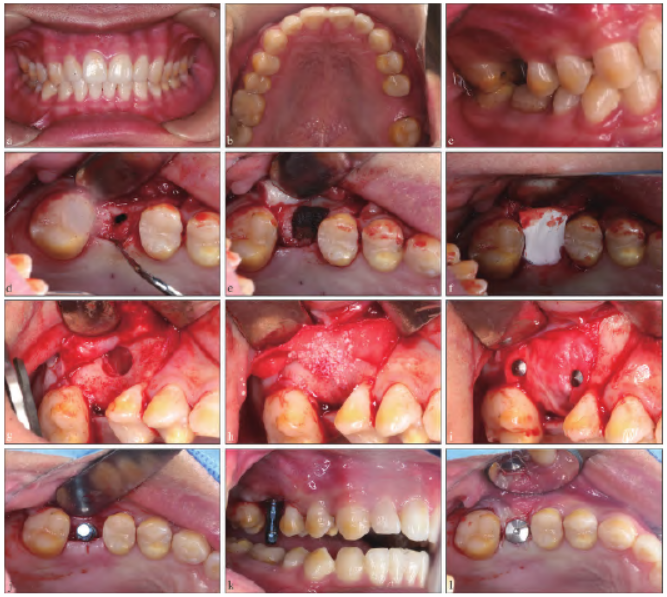

16 牙缺失,牙龈状况良好,未见瘘道,缺牙区近远中距10 mm,邻牙、对牙合牙未见异常(图1a~c)。

1.5.1 恢复上颌窦与原拔牙窝相通处骨缺损

切开翻瓣,可见与影像检查一致的骨缺损区与上颌窦相通,且探及上颌窦底黏膜不完整,捏鼻鼓气试验呈阳性,彻底搔刮去除肉芽组织,去除牙槽骨穿通隧道内及上颌窦底骨板处的肉芽组织,于交通隧道内填塞胶质银明胶

海绵至窦底处,于牙槽嵴顶表面覆盖Bio-Gide 胶原膜(Geistlich 公司,瑞士)(图1d~f)。术后3 个月CBCT 示上颌窦底完整、有连续性,窦嵴距2 mm(图2b、e)。

1.5.2 恢复垂直向骨缺损

3 个月后行上颌窦外提升术:小范围开窗,充分完整剥离,捏鼻鼓气试验呈阴性,将Bio-Gide胶原膜的一部分置入窦底处用以保护反复穿通的黏膜,植入Bio-oss 骨粉(Geistlich 公司,瑞士)后,将另一部分暴露于外侧壁的Bio-Gide 胶原膜于颊侧反折后膜钉固定(图1g~i)。术后10 个月CBCT 示16 牙术区窦底内可见高密度影像,成骨良好,可用骨高度约11 mm(图2c、f)。

1.5.3 骨量恢复后行种植修复

待上颌窦外提升术后10 个月于16 牙处植入士卓曼4.8 mm×10 mm RNSP TiZr 种植体(Straumann集团,瑞士) 1 枚,植入扭矩30 N.cm,旋入愈合基台,3 个月后行冠修复(图3a~b)。

图 1 口内资料。a~c:术前口内照;d:牙槽嵴顶处骨缺损与上颌窦相通;e:填塞胶质银明胶海绵至窦底;f:覆盖Bio-Gide 胶原膜;g:3 个月后行上颌窦外侧壁开窗、黏膜完整;h:Bio-Gide 胶原膜的一部分置入窦底,植入Bio-oss 骨粉;i:Bio-Gide 胶原膜的另一部分于颊侧反折后膜钉固位;j~l:种植体植入。